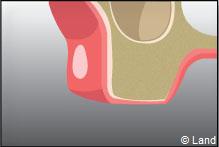

Certaines dents n’arrivent pas à faire leur éruption sur l’arcade correctement, présentent un accès difficile (dents de sagesses), ont des racines divergentes ou très courbées, ou sont considérablement abîmées (carie importante par exemple). Aussi elles restent souvent en partie ou totalement incluses dans l’os. On procède alors à une extraction chirurgicale.

L’intervention commence là aussi par une anesthésie locale, puis le chirurgien-dentiste procède à une incision de la gencive et à un dégagement du tissu osseux autour de la dent.

Parfois cette dernière est sectionnée pour ne pas traumatiser l’os souvent responsable de suites opératoires douloureuses.

Une fois la dent enlevée, la cavité est nettoyée. En cas d’une dent souffrant d’inflammation, le tissu infecté sera également enlevé.